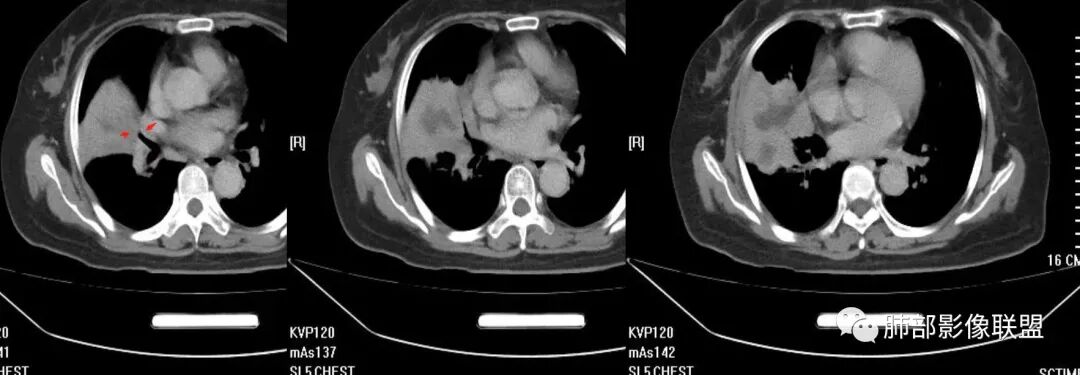

这个病灶中叶、下叶都有

坏死腔是连通的

这个支气管局部堵了,但是远端支气管走形自然,腔内粘液栓

这个病例,看长轴、形态,首先跨叶,里面的坏死腔,它是相通的,就是跨中叶及前基底段。

看中叶外侧段的病变,我观察到支气管与坏死腔相通的,支气管这种堵塞就不踏实了,假如是腔内的病变,就不太支持。

如果是腔内的病变,第一,应该是局限在某个叶的,不可能上下叶都有。所以不太支持腔内的病变。因此考虑腔外的病变。腔外局限的肿瘤肯定不符合,假如这个病灶是个局限大肿块的话,里面肺动脉走势还可以。

然后中叶与下叶的坏死腔病灶是相通的,病灶是跨叶的,胸膜糊墙为主。